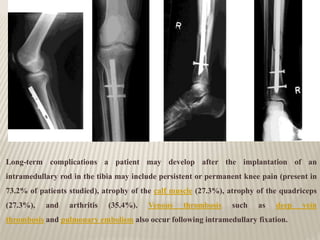

Long-term complications a patient may develop after the implantation of an

intramedullary rod in the tibia may include persistent or permanent knee pain (present in

73.2% of patients studied), atrophy of the calf muscle (27.3%), atrophy of the quadriceps

(27.3%), and arthritis (35.4%). Venous thrombosis such as deep vein

thrombosis and pulmonary embolism also occur following intramedullary fixation.